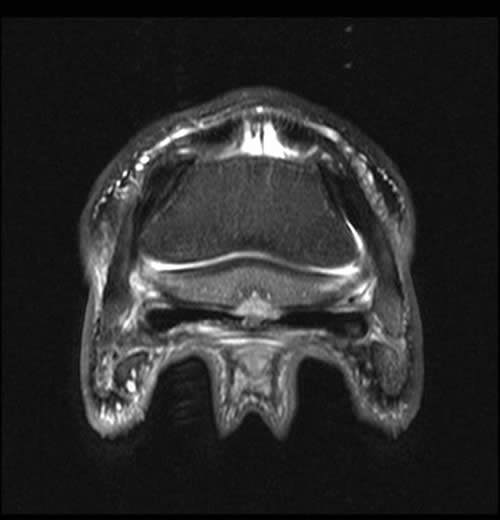

Figure 2: Transverse 2D STIR image of the same horse as shown in figure 1. There is focal degeneration of the DDFT and focal palmar cortical lysis (arrow). Adhesion formation between the palmar cortex and DDFT is likely and there is mild medullary oedema of the navicular bone.